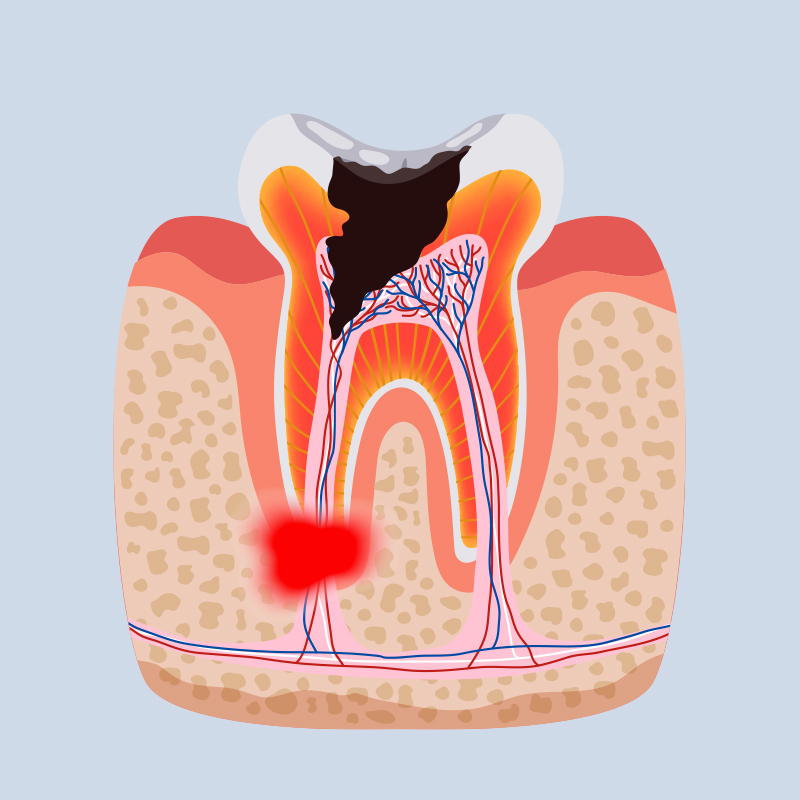

- When you have a stained or discoloured tooth

- When your tooth is worn out, chipped or broken

- When you have finished a root canal on your one of your front teeth